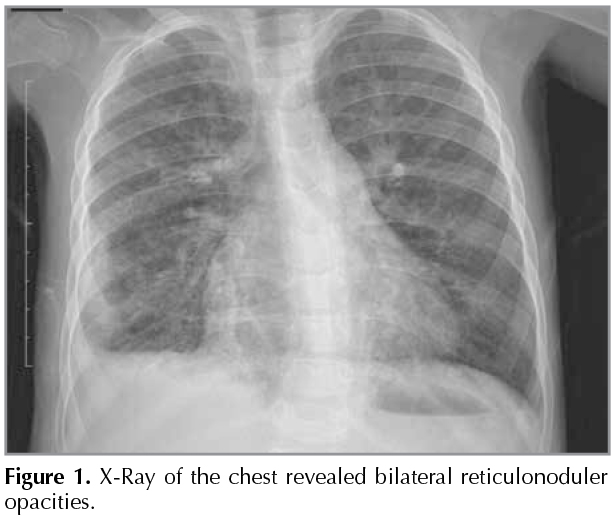

A 5-week-old female with common variable immunodeficiency (CVID) presented with lower respiratory tract infection. X-Ray of the chest showed ground glassed opacities and multiple nodules evident in the left and right lung suggestive of an interstitial lung disease (Figure 1). Lung biopsy was performed. Hematoxylin and eosin stained sections showed areas of consolidation with numerous foamy histiocytes. Some of the alveolar spaces were lined by large cells, containing eosinophilic inclusion bodies (Figure 2A), surrounded by a characteristic halo which was positive for CMV immunohistochemical stain (Figure 2B). Histopathology of the lung biopsy showed CMV pneumonia. Clinical status improved after starting antiviral treatment. CMV pneumonia is one of the most important opportunistic pathogens in immunocompromised patients (1). CMV induced pulmonary lesions exhibit diffuse alveolar damage and/or interstitial inflammation and further prevent pulmonary interstitial fibrosis (2).

Figure 2A-B